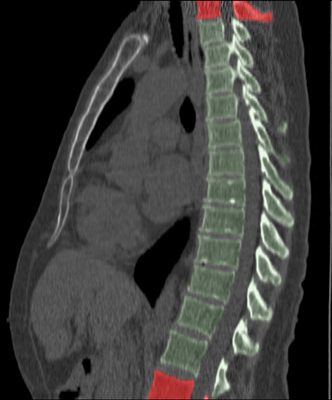

We trained and evaluated the method with five sets of CT and MR scans that visualize the spine. Reference segmentation masks for four of these datasets are publicly available, which allowed for a comparison with other publications that used the same data. Examples of images from the datasets are shown in Figure 3.

The thoracolumbar spine CT dataset consists of 15 dedicated spine CT scans that visualize all thoracic and lumbar vertebrae. It was originally used for the spine segmentation challenge held in conjunction with the Computational Spine Imaging (CSI) workshop at MICCAI 2014 (Yao et al., 2016). All subjects were young adults ( years) without vertebral fractures who were scanned with IV-contrast administration. The scans were reconstructed to in-plane resolutions of and slice thicknesses of . Semi-automatically obtained reference segmentations were provided by the challenge organizers. To allow for a comparison with the challenge results, we used the same data split with 5 scans for evaluation and the remaining 10 scans for training and development.

The xVertSeg.v1 dataset consists of 15 lumbar spine CT scans of subjects with compression fractures of various grades and types (Ibragimov et al., 2017). Manual reference segmentations are available for the lumbar vertebrae and were defined through a consensus reading of two observers. The scans were reconstructed to in-plane resolutions of and slice thicknesses of . There are currently two other publications that used the same dataset, but with different evaluation/training separation (Janssens et al., 2018; Sekuboyina et al., 2017). We therefore used the scans for evaluation and the remaining 10 scans for training.

The low-dose chest CT dataset consists of 55 scans from the National Lung Screening Trial (The National Lung Screening Trial Research Team, 2011). These scans were acquired for lung imaging and visualize in addition to the lungs a variable section of the thoracic and upper lumbar vertebrae. The scanned subjects were heavy smokers aged 50 to 74 years and therefore at increased risk for vertebral compression fractures due to their advanced age and smoking history. The scans were acquired with low radiation dose and reconstructed to in-plane resolutions of and slice thicknesses of . We created manual and semi-automatic reference segmentations for this dataset: 10 scans were used for evaluation and were therefore fully manually annotated by drawing along the contour of each vertebra in sagittal slices using an interactive live wire tool (Barrett and Mortensen, 1997). The contours were converted into segmentation masks, in which inaccuracies and other mistakes were corrected voxel-by-voxel. An additional set of 5 scans was annotated in the same way and was used to train a preliminary version of the network. This network was used to predict rough segmentations in the remaining 40 scans. These rough segmentations were manually inspected and corrected voxel-by-voxel, and were used for training of the final network. This strategy enabled us to create a large training set with substantially less manual annotation effort compared to fully manual segmentation, which is not necessarily needed for training data. Additionally, a second observer fully manually annotated two scans from the evaluation set for an estimation of the interobserver agreement. All fully manual and semi-automatic segmentations were performed in sagittal views by observers who received detailed instructions beforehand. Additionally, all segmentations were validated by an experienced radiologist.

The lumbar spine CT dataset consists of 10 scans of healthy subjects and corresponding manual reference segmentations of the lumbar vertebrae (Ibragimov et al., 2014; Korez et al., 2015). The scans were reconstructed to in-plane resolutions of and slice thicknesses of . Because this dataset is the smallest of the datasets that we included, it was used for an external evaluation of our supervised approach. Scans from this dataset were therefore only used for evaluation and were not part of the training set.

The lumbar spine MR dataset consists of 23 T2-weighted turbo spine echo MR images acquired at 1.5T in sagittal orientation (Chu et al., 2015). The scans have a resolution of . Manual reference segmentations are available for 7 vertebrae (T11-L5) in all scans. These reference segmentations contain only the vertebral bodies, not the entire vertebrae.